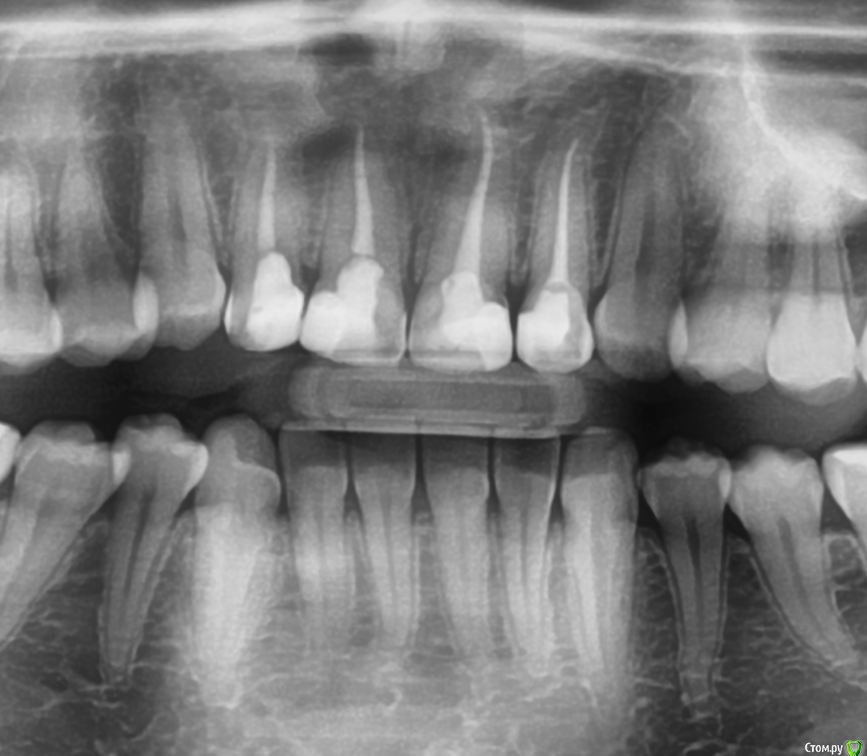

Puppy_Blue Опубликовано 27 марта, 2017 Поделиться Опубликовано 27 марта, 2017 Здравствуйте. Уважаемые врачи, помогите, пожалуйста, разобраться в том "кто прав, а кто виноват". Один врач-стоматолог говорит "есть штифты на передних зубах", другой - нет. Или может быть по этому снимку вообще невозможно увидеть их наличие или отсутствие? Ссылка на комментарий

shishok Опубликовано 27 марта, 2017 Поделиться Опубликовано 27 марта, 2017 Штифтов не вижу. 4 Ссылка на комментарий

Zlata-doctor Опубликовано 27 марта, 2017 Поделиться Опубликовано 27 марта, 2017 штифтов нет. А надо? 1 Ссылка на комментарий

AndyAndy Опубликовано 28 марта, 2017 Поделиться Опубликовано 28 марта, 2017 Я ортопед, выскажу своё мнение. Зубы восстановлены на 70% пломбами, тут однозначно коронки и однозначно культевые вкладки. Под установкой Сирона скорее всего предполагается кад/кам изготовление. Тут есть ньюанс по прозрачности этих коронок, а именно проницаемость для культевых вкладок. Вкладки лучше делать из драгметаллического сплава (если бюджет позволяет), они желтоватого цвета и будет норм. Обсудите с вашим доктором эти вопросы 1 1 Ссылка на комментарий